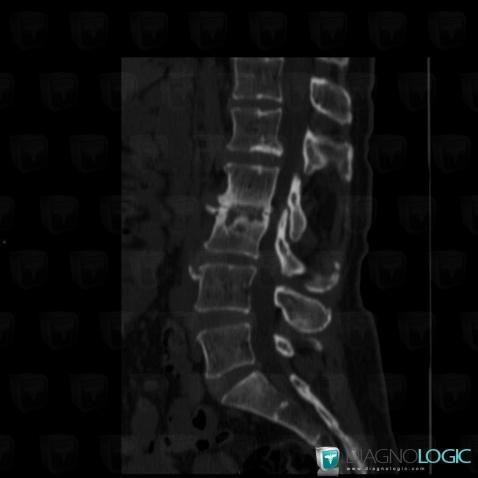

Discopathie dégénérative, Corps vertébral / Disque, Scanner

- Diagnostic Discopathie dégénérative, Localisation(s) Corps vertébral / Disque, comportant les gammes Condensation en bande des plateaux vertébraux, Lésion discale